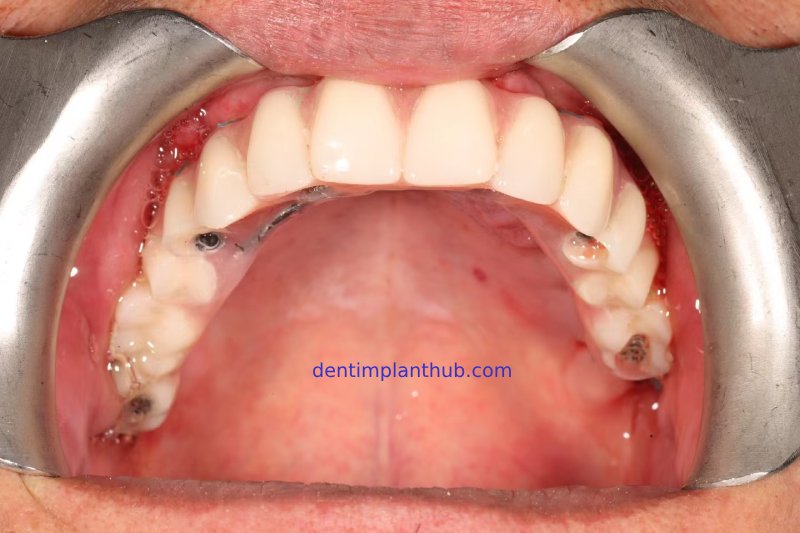

Photos of the temporary dental crown placed in the mouth

Photos of the permanent crown placed in the patient's mouth